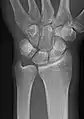

• Wrist - DP and Lateral

• Scaphoid - DP with Ulna deviation, Lateral, Oblique and DP with 30° angulation